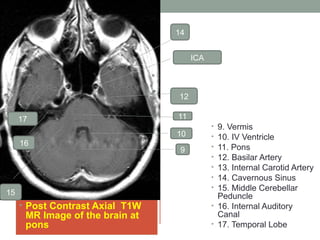

• Post Contrast Axial T1W

MR Image of the brain at

pons

• 9. Vermis

• 10. IV Ventricle

• 11. Pons

• 12. Basilar Artery

• 13. Internal Carotid Artery

• 14. Cavernous Sinus

• 15. Middle Cerebellar

Peduncle

• 16. Internal Auditory

Canal

• 17. Temporal Lobe